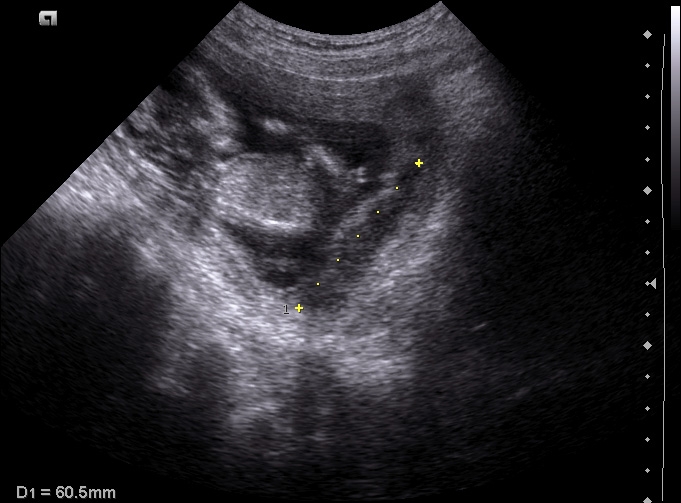

Optymalny wiek ciążowy dla pierwszego badania prenatalnego zawiera się między 11-13+6 tygodniem ciąży, długość ciemieniowo-siedzeniowa (CRL) musi się mieścić między 45 a 84 mm. Poza stwierdzeniem ciąży żywej, można określić jej dokładny wiek, stwierdzenie obecności dużych wad płodu, a w ciąży mnogiej ocena ilości płodów, kosmówkowości.